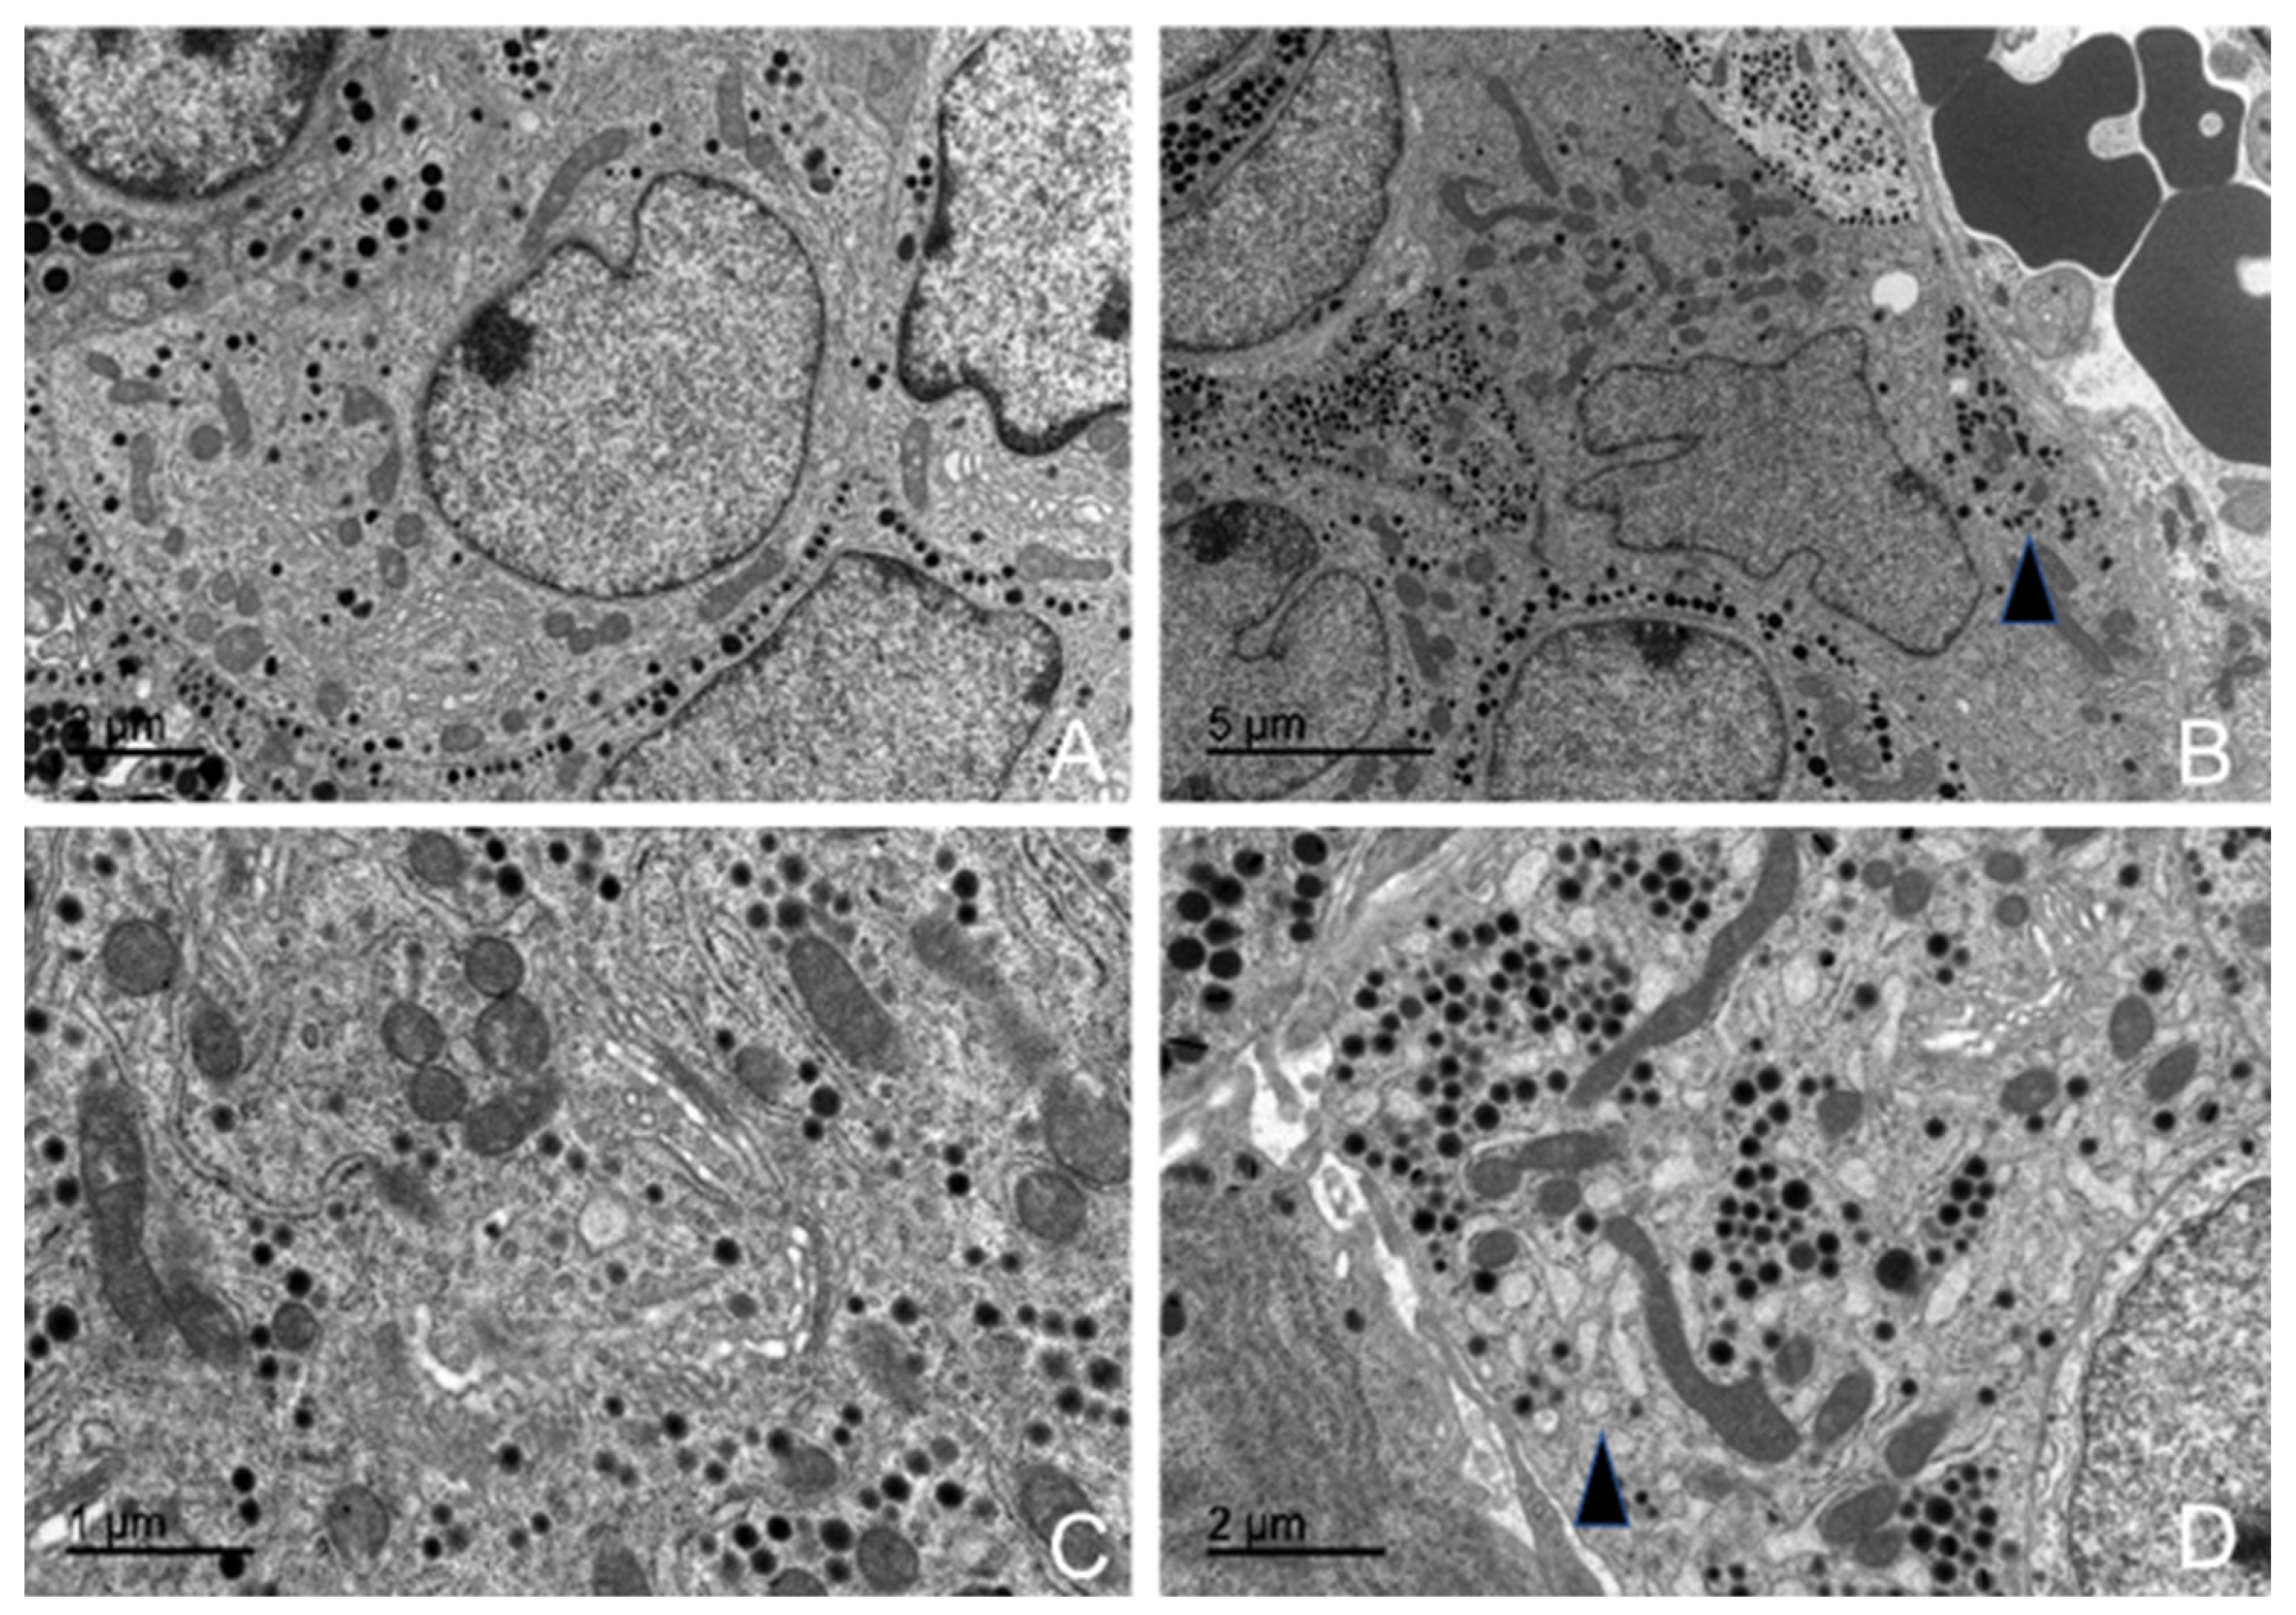

3.5.1. Corticotrophs (ACTH-Producing Cells)

3.5.2. Lactotrophs (LTH-Producing Cells)

3.5.3. Somatotrophs (GH-Producing Cells)

3.5.4. Gonadotrophs (GnRH -Producing Cells)